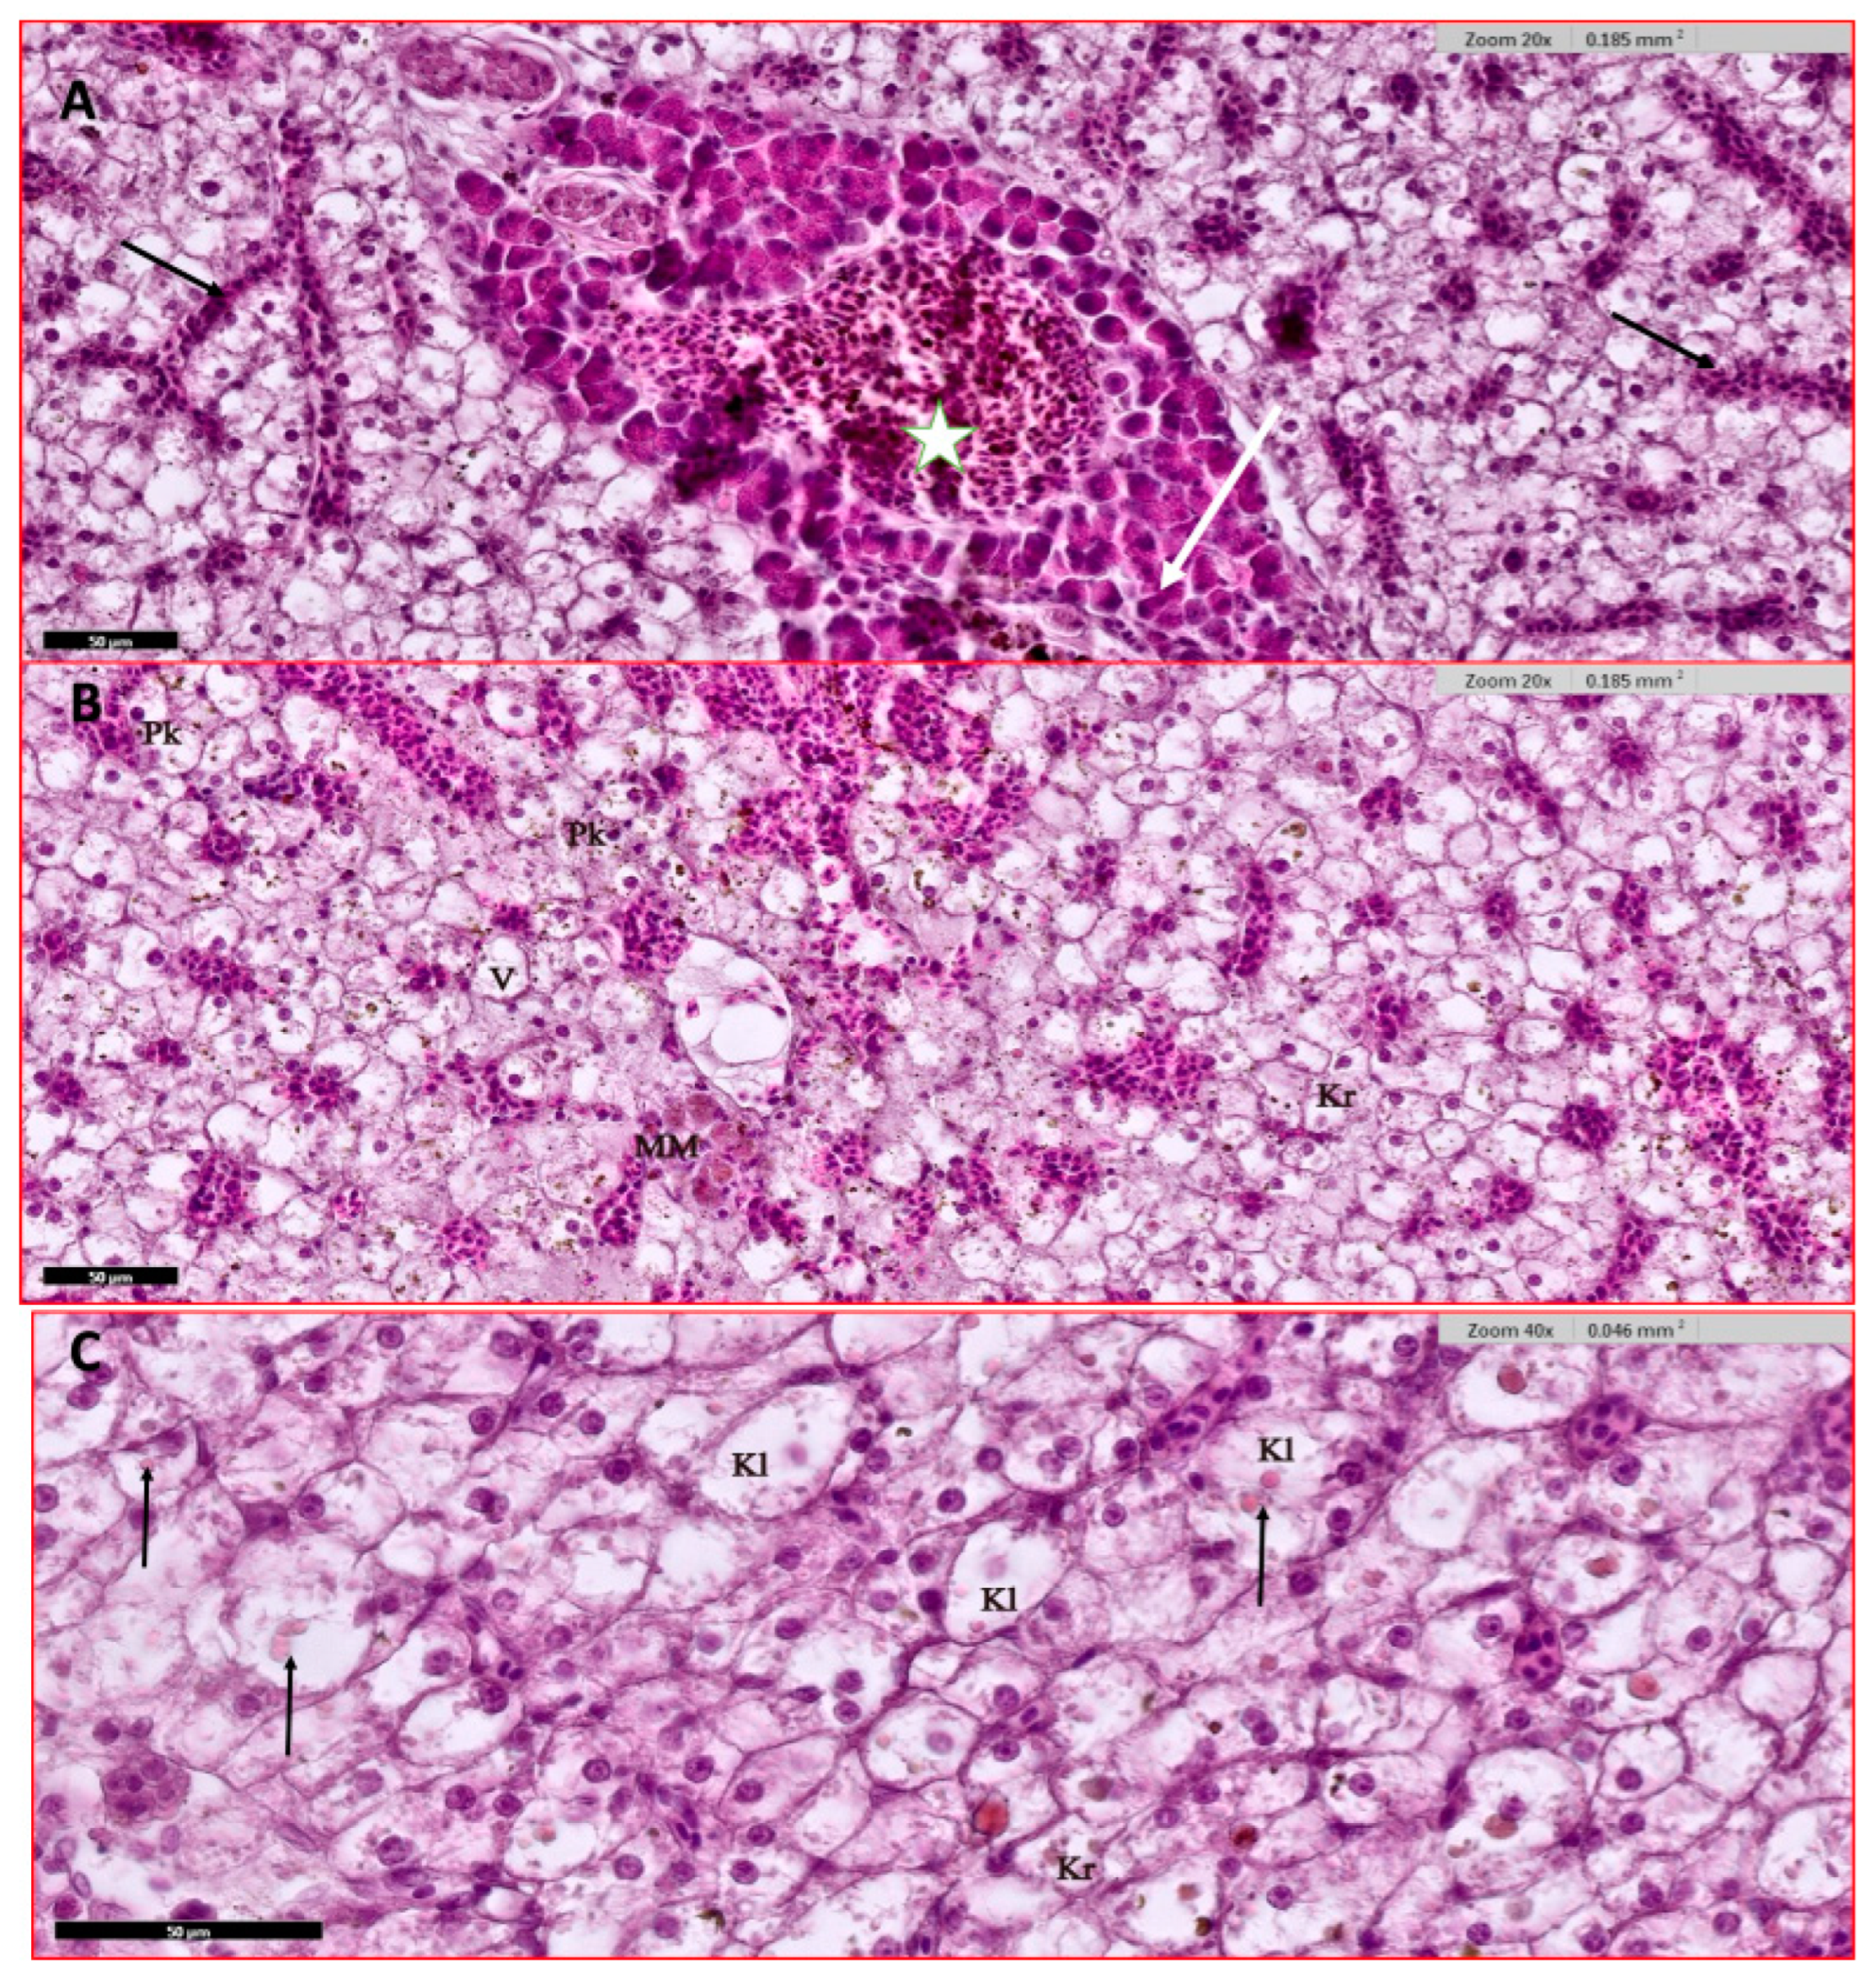

3.4.1. Liver and Hepatopancreas